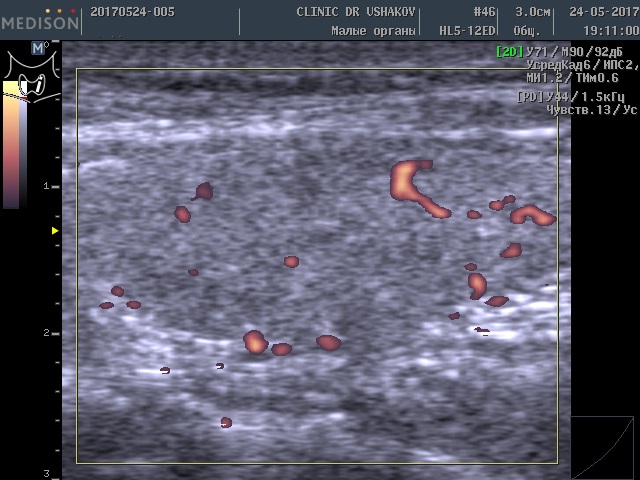

2) что усиленный кровоток в щитовидной железе (при УЗИ) ― признак перенапряжения и интенсивного образования гормонов тканью железы.

Обратите внимание на активность кровотока по данным УЗИ у этой пациентки (рис. 3 и 4).

Рисунки 3 и 4. Пациентка А., 26 лет левая и правая доли щитовидной железы в режиме ЭДК. Кровоток в малой и умеренной степени усилен (обозначен красным цветом).